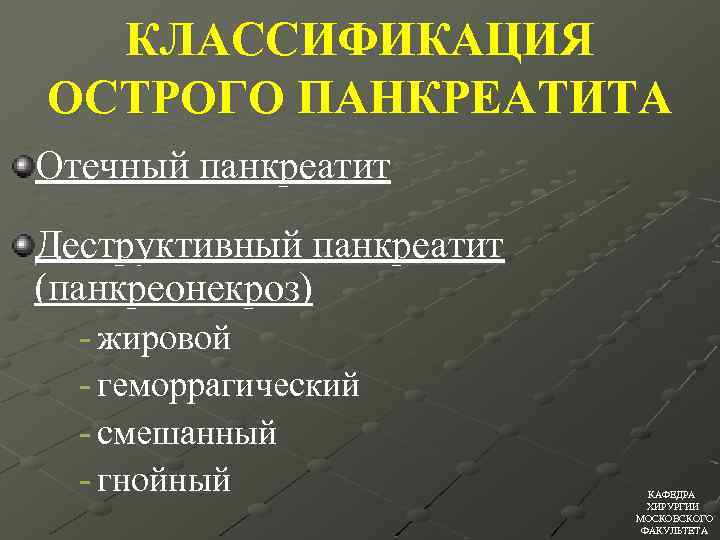

КЛАССИФИКАЦИЯ ОСТРОГО ПАНКРЕАТИТА Отечный панкреатит Деструктивный панкреатит (панкреонекроз) - жировой - геморрагический - cмешанный - гнойный КАФЕДРА ХИРУРГИИ МОСКОВСКОГО ФАКУЛЬТЕТА

КЛАССИФИКАЦИЯ ОСТРОГО ПАНКРЕАТИТА Отечный панкреатит Деструктивный панкреатит (панкреонекроз) - жировой - геморрагический - cмешанный - гнойный КАФЕДРА ХИРУРГИИ МОСКОВСКОГО ФАКУЛЬТЕТА